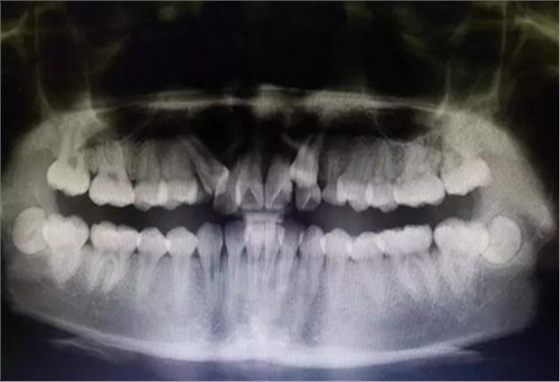

全景片